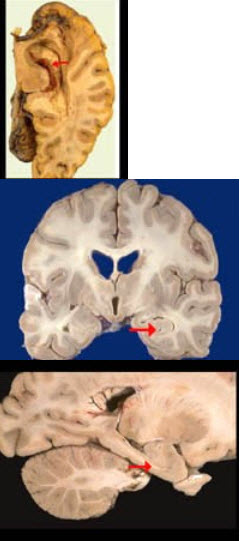

如图箭头所示为大脑哪个部位( )

A:壳核

B:丘脑

C:尾状核

D:岛叶

E:海马